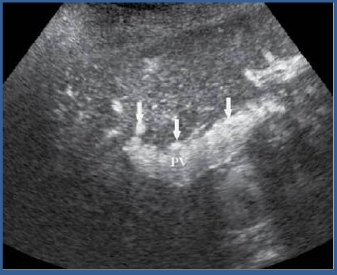

patent TIPS

clotted TIPS